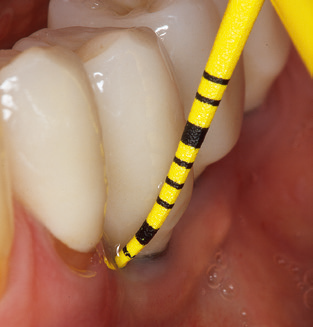

The current working concept for SPT

Updating the patient’s medical history is an important aspect of SPT and should occur at least once per year. It helps the dental team to identify and document any new risk factors. Especially when a patient is treated over many years, it is important to establish whether patient-specific and general health risk factors have changed. This primarily concerns a heightened risk as a result of diabetes, but other general conditions (cardiovascular disease and neoplasia) can also produce a modified risk profile as a result of the treatment performed and medication administered. Accordingly, updating the medical history as part of SPT is very important, as a modified risk profile may trigger the need to adapt the treatment interval. In the next step, it is important to afford the diagnostics due attention. Whilst instruments are a central aspect of SPT, findings and their documentation must never be neglected. The periodontological findings are essential for a good diagnosis; increases in the pocket depths and the BOP index are clear indicators of advancing periodontal and peri-implant disease. As such, the team should not shy away from probing implants too, with the aim of gathering the requisite data. At the same time, it is important to use periodontal probes with millimetre markings. Metallic probes have already been used for determining pocket depths around natural teeth for decades. In the case of implants, the challenge of recording correct and reproducible pockets depths is even greater. As the discrepancy between the implant diameter and the contour of the superstructure regularly results in overcontouring of the superstructure, flexible probes which still feature millimetre markings are a sensible solution for measuring pocket depths around implants (e.g., Colorvue Kit PCV11KIT6, Hu­Friedy; Fig. 4).